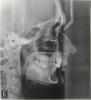

zaharik1980 Опубликовано 30 октября, 2012 Поделиться Опубликовано 30 октября, 2012 (изменено) Здравствуйте, мне 32 года,начала лечение брекетами даймон дистального прикуса, класс Эйгеля II, патологическия стираемость НЧ и ВЧ. План такой: ВЧ фиксация в сентябре 2012, НЧ фиксация -декабрь 2012, аппарат Гербста - февраль 2013 . Уверяют, что прикус улучшиться, но идеального смыкания не будет. Я на это согласна, лишь бы хуже не стало. Подскажите пожалуйста, не упадет ли у меня совсем прикус и не разболтаю ли я сустав. Боюсь, как бы не получить боОльшие проблемы с ВЧС.К сожалению, ОПГ снимка нет на руках, а ТТГ только фото.Заранее благодарю за внимание к моей проблеме! Изменено 30 октября, 2012 пользователем zaharik1980 Ссылка на комментарий

shoma Опубликовано 30 октября, 2012 Поделиться Опубликовано 30 октября, 2012 проблема с прикусом это не главное, у Вас увеличен скелетный размер верхней челюсти, наверняка есть проблемы с суставом (нужны другие снимки чтобы точно сказать).Никакие брекеты здесь не помогут, Ваш случай хирургический. не теряйте зря время, лучше узнайте про ортогнатическую хирургию. Ссылка на комментарий